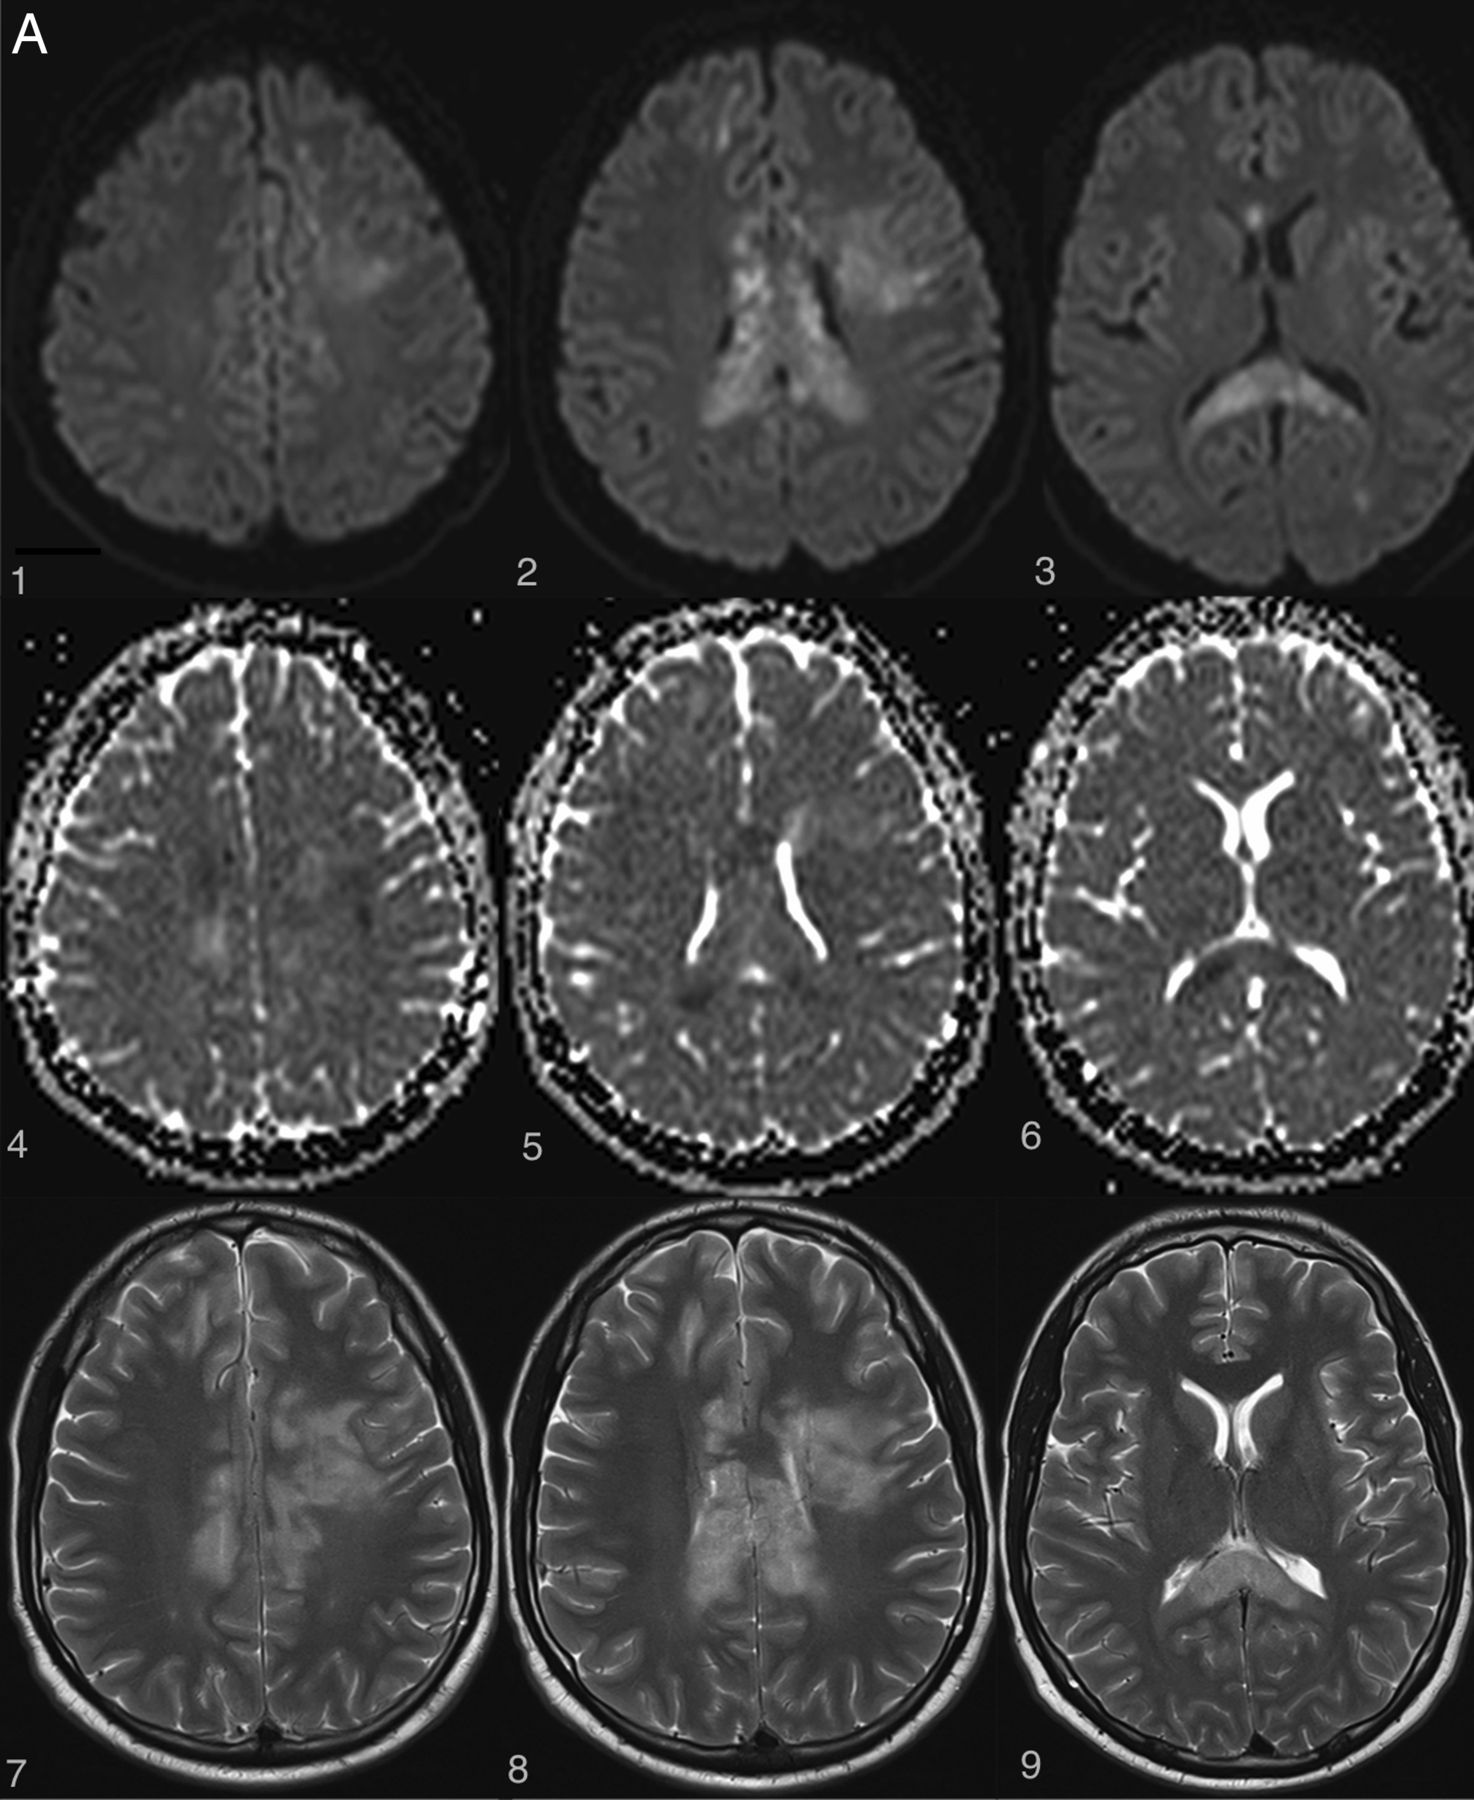

Examples of irreversible brain and spinal cord lesions due to decompression sickness (A, B, and C are taken from the same patient). A, On DWI (1, 2, 3, 4, 5, 6), the areas of restricted diffusion correspond to lesions of the corpus callosum and frontal white matter on both sides. They appear as high signal on T2WI (7, 8, 9). B, Sagittal (1 and 2, white arrows) and axial (3 and 4, white arrows) T2WI shows a cervicothoracic (C7–T1) lesion appearing as high signal without contrast enhancement on T1WI (2). C, On follow-up 1 month later, the lesions described in A and B are still present on these brain (1, 2, 3, 4) and spine (5, 6) images. Note the enhancement of the corpus callosum (3 and 4). Lesions of the right frontal deep white matter and corpus callosum have healed and now appear as “little cavities.” Similar features are usually seen in ischemic or necrotic lesions of the central nervous system.